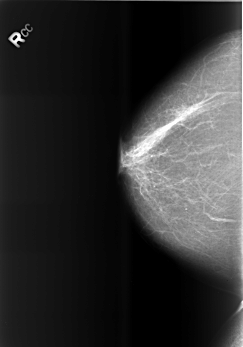

B_3466_1.RIGHT_CC

RIGHT_CC LINES 5552 PIXELS_PER_LINE 3880 BITS_PER_PIXEL 12 RESOLUTION 50 NON_OVERLAY

FILE: B_3466_1.LEFT_CC.OVERLAY

TOTAL_ABNORMALITIES 2

ABNORMALITY 1

LESION_TYPE CALCIFICATION TYPE PLEOMORPHIC-FINE_LINEAR_BRANCHING DISTRIBUTION CLUSTERED

ASSESSMENT 4

SUBTLETY 2

PATHOLOGY BENIGN

ABNORMALITY 2

LESION_TYPE CALCIFICATION TYPE PLEOMORPHIC DISTRIBUTION CLUSTERED

SUBTLETY 4